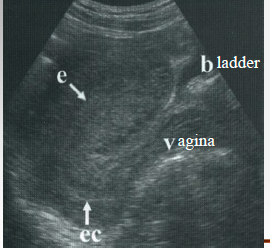

What didn’t the patient do based on this image?

fill her bladder

Do before barium studies Full bladder (32 oz of H2 O 1 hour prior to exam). Optimal when it covers fundus and flattens uterus enough to visualize it and adnexa well